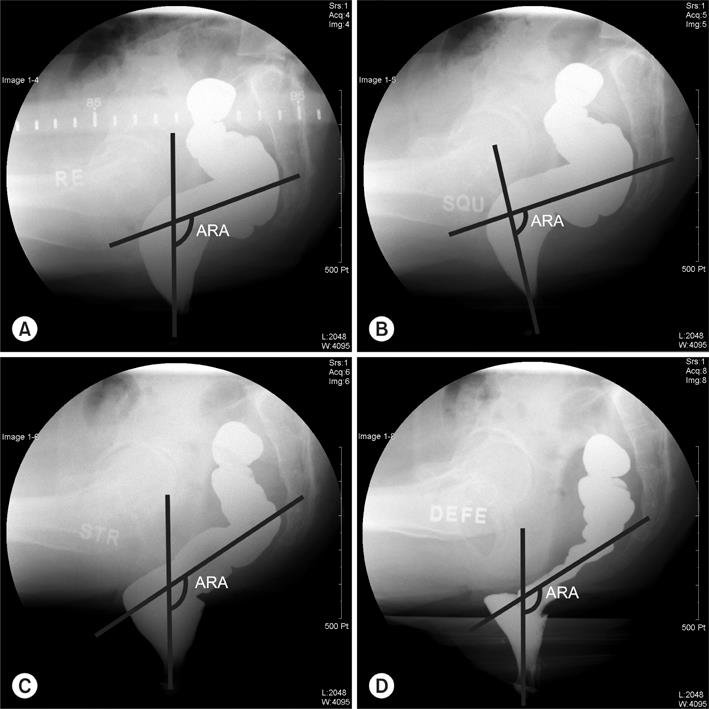

• Kiçik rektoselləri təyin etmək və dərəcəni dəqiqləşdirmək üçün defekoqrafiya edilir(Şəkil2).

duz img 23

Şəkil 2. Defekoqrafiya